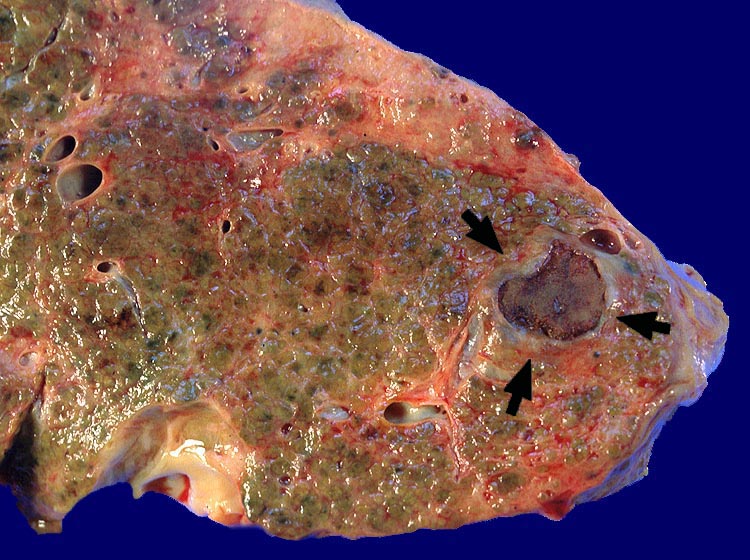

nekrotisches Hepatozelluläres Karzinom geheilt durch Alkoholinjektion

Fibrös abgekapseltes vollständig nekrotisches hepatozelluläres Karzinom. Feinknotiger zirrhotischer Umbau.

Zirrhose bei chronischer Hepatitis C und Alkoholabusus. St.n. Alkoholinjektion in einen solitären Herd eines hepatozellulären Karzinoms vor 3 Jahren.